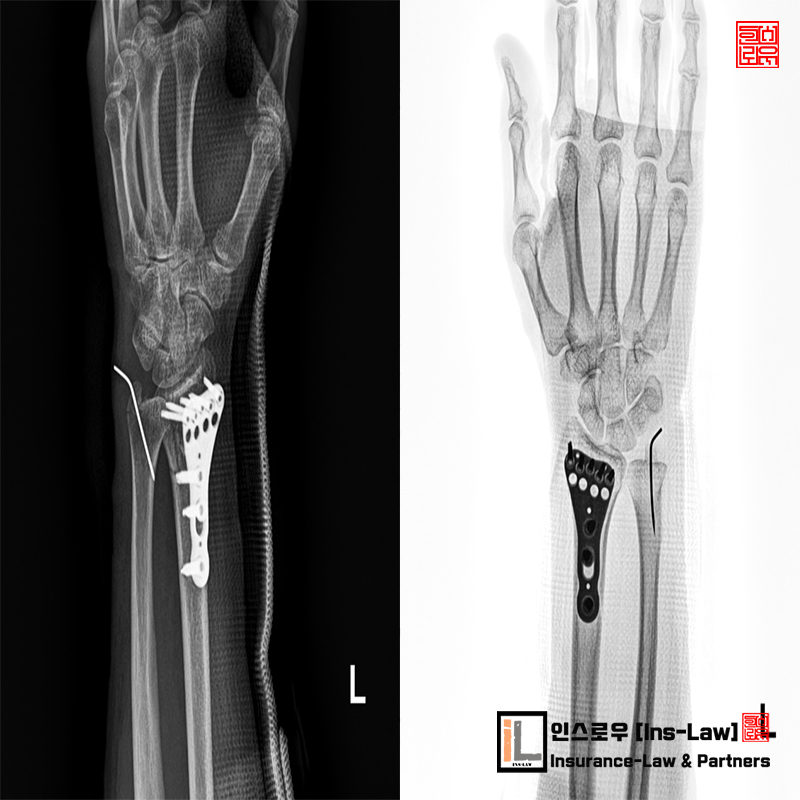

¼Õ¸ñ°ñÀýÀÇ »ç°íÀ¯ÇüÀº ´ëºÎºÐ ³ôÀº °÷¿¡¼ ¶³¾îÁú¶§ ¹Ý»çÀûÀ¸·Î ¸öÀ» ÁöÅÊÇϱâ À§ÇÑ ¹Ý»çÀûÀÎ ¹æ¹ýÀ¸·Î üÁßÀ» À̱âÁö ¸øÇÏ°í ¼Õ¸ñÀÌ °ñÀýµÇ´Â »ç·Ê°¡ °¡Àå ÈçÇÏ°Ô ÀϾ´Â °ñÀý»ç°íÁß¿¡ ÇϳªÀÔ´Ï´Ù. ¼Õ¸ñ¿¡¼ ¹ß²ÞÄ¡±îÁöÀÇ »À´Â ¿ä°ñ°ú ô°ñ °¢ 2°³ÀÇ »À°¡ À§Ä¡Çϰí ÀÖ½À´Ï´Ù.±ä Àå°ñÀ» ¿ä°ñÀ̶ó°í ÇÏ¸ç ¹Ý´ëÃø »À°¡ ô°ñÀÔ´Ï´Ù. ¿ä°ñÀ©À§ºÎ °ñÀýÀº ½ÉÀå¿¡¼ ¸Õ ÂÊÀ» ¿øÀ§ºÎ·ÎÇÏ¸ç °ñÀýºÎÀ§°¡ ¿ä°ñÀ̱⿡ ¿ä°ñ¿øÀ§ºÎ °ñÀýÀ̶ó°í ÇÕ´Ï´Ù. ¿ä°ñ°ú ô°ñÀÇ ±â´ÉÀº ÆÈ¿¡ ±¼½Å¿îµ¿°ú ȸÀü¿îµ¿À» ÀÌ·ç±â¿¡ °ñÀýÀÌÈÄ ÀçȰġ·á°¡ »ó´çÈ÷ Áß¿äÇÏ´Ù°í ÇÒ ¼ö ÀÖ½À´Ï´Ù.

¨ç ¿ìÃø Àü¿ÏºÎ Á¤Áß½Å°æ ¹× Ã¶°ñ½Å°æ ÆÄ¿

¨è ¿ìÃø ³»Ãø ¹× ¿ÜÃø Àú¿ÏºÎ Ç¥Àç½Å°æ ÆÄ¿

¨é ¿ìÃø Àü¿ÏºÎ ¿ä°ñ ¹× ö°ñ µ¿¸ÆÆÄ¿

¨ê ¿ìÃø Àü¿ÏºÎ ¼öÁö ¹× ¼ö±Ù ±¼°Ç ÆÄ¿